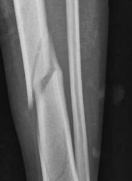

Standard orthogonal radiographs (anteroposterior and lateral) are insufficient for evaluating tibial fractures with suspected plafond extension. A dedicated computed tomography (CT) scan of the ankle with coronal, sagittal, and 3D reconstructions is mandatory.

The CT scan serves several critical functions. First, it identifies the exact location and orientation of the articular split. Second, it dictates the trajectory of the independent articular lag screws, ensuring they are placed perfectly perpendicular to the fracture plane. Third, and perhaps most importantly, it allows the surgeon to map the safe zones for these lag screws so they do not obstruct the planned path of the intramedullary nail.